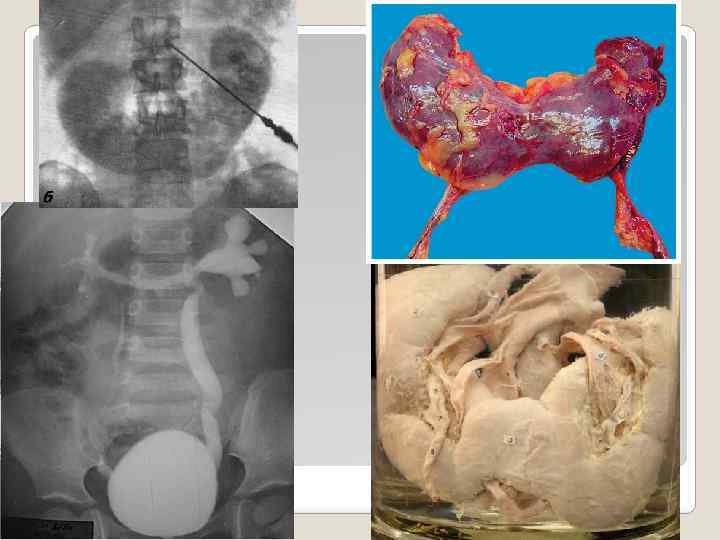

Поликистоз - наследственная и всегда двусторонняя аномалия, в результате чего возникает задержка мочи в проксимальных отделах нефронов с последующим расширением слепо заканчивающихся канальцев и образованием из них кист. Иногда для уточнения диагноза выполняют ретроградную пиелографию и ангиографию; радиоизотопные методы диагностики позволяют количественно определить площадь функционирующей паренхимы.

Поликистоз - наследственная и всегда двусторонняя аномалия, в результате чего возникает задержка мочи в проксимальных отделах нефронов с последующим расширением слепо заканчивающихся канальцев и образованием из них кист. Иногда для уточнения диагноза выполняют ретроградную пиелографию и ангиографию; радиоизотопные методы диагностики позволяют количественно определить площадь функционирующей паренхимы.

Мультикистоз - односторонний порок, образуемый вследствие отсутствия закладки мочеточникового зачатка при сохранении фильтрационно-реабсорбционного аппарата метанефроса. Лечение заключается в нефрэктомии почки, целиком состоящей из кист и фиброзной ткани ("гроздь винограда").

Мультикистоз - односторонний порок, образуемый вследствие отсутствия закладки мочеточникового зачатка при сохранении фильтрационно-реабсорбционного аппарата метанефроса. Лечение заключается в нефрэктомии почки, целиком состоящей из кист и фиброзной ткани ("гроздь винограда").